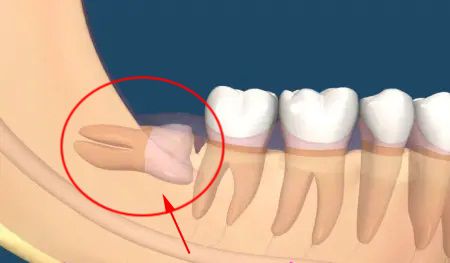

△傳統的鑿骨劈冠法拔智牙,手法簡單粗暴。

不少人談拔智牙“色變”。因爲傳統采用鑿骨劈冠法,需要利用錘子、鑿子、牙挺、鉗子等,對智牙進行增隙、去骨和分牙操作。因錘擊的力度和方向難以把握,易對鄰牙、骨闆、颌骨神經等造成損傷,增加斷根進入周圍組織中的概率。患者痛感強,術後并發症多。